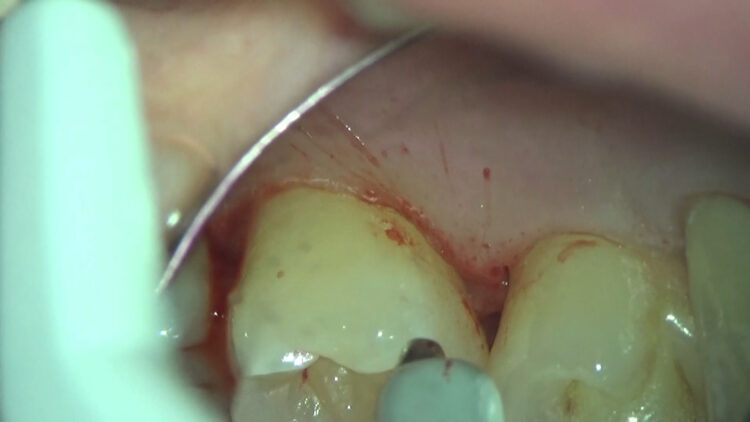

歯石除去後